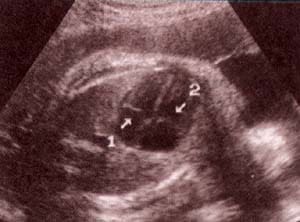

| fig 33.– (a). tractos de salida. 36 semanas. ventrículo derecho (1). arteria pulmonar (2). | fig. 33.-(b).ventrículo izquierdo (3). aorta (4). |